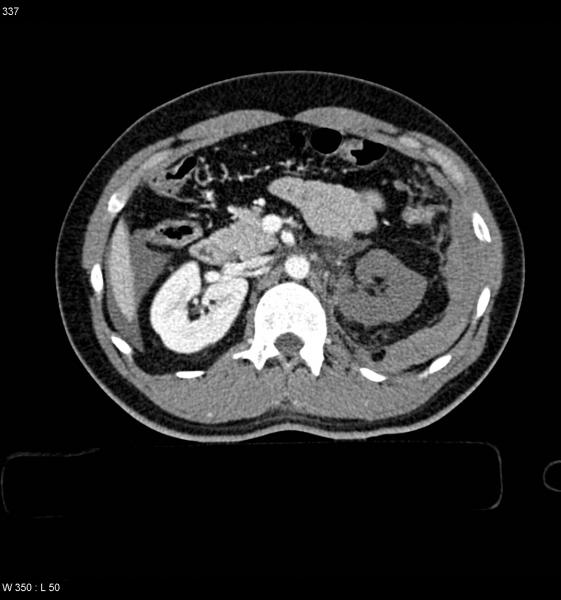

Isquemia mesentérica: Aguda y crónica